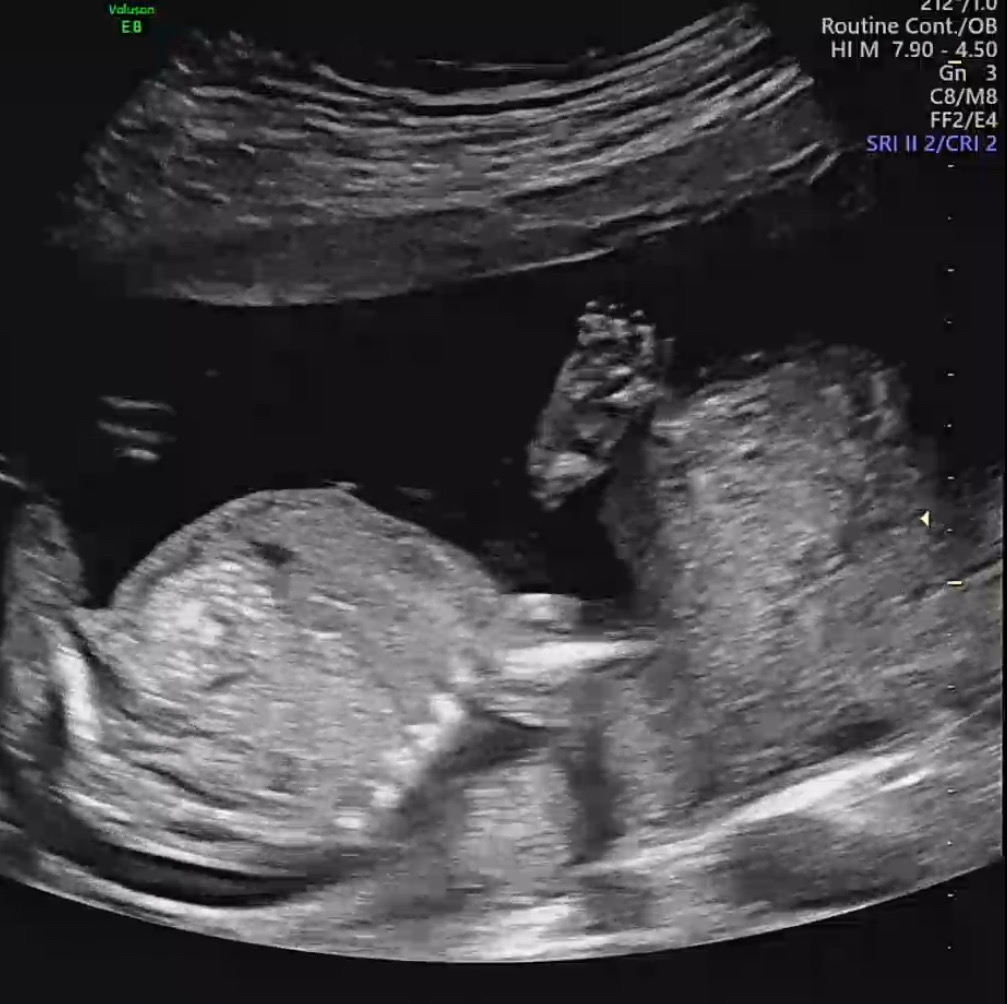

17주 아가 손 빠는 모습 ㅎ

ㅎㅎ 마구 손으로 주먹질 하더니 쪽쪽쪽 입으로 가져가네요 ㅎㅎ